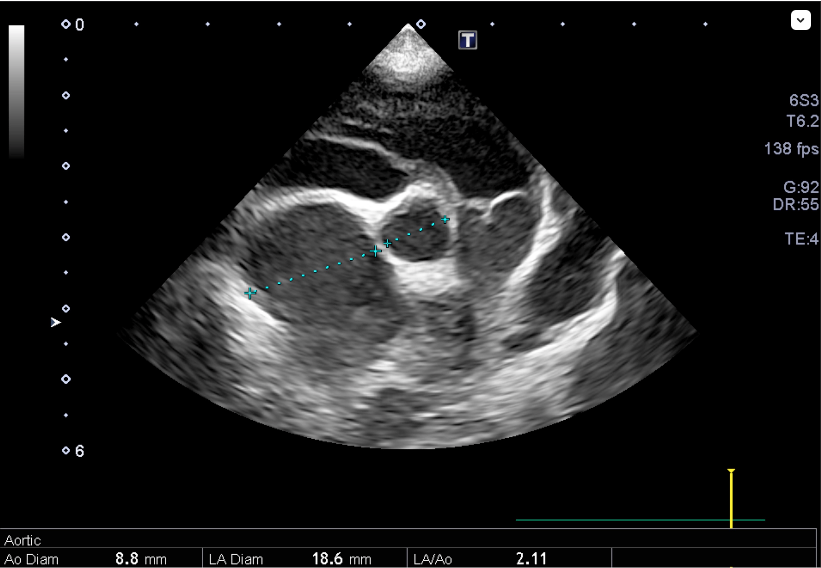

心臓エコー内服開始0日目

心臓エコー内服開始3年目 フロセミド開始

心臓エコー内服開始6年目